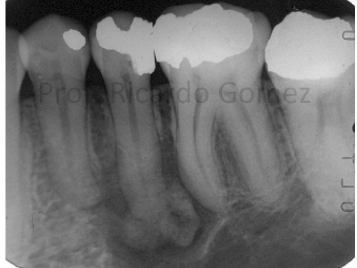

central giant cell granuloma occlusal radiograph of mandible

may demonstrate CGCG as cause of expansion of internal and external cortical bones

central giant cell granuloma maxillary occlusal radiograph

demonstrates CGCG as cause of divergence of roots of maxillary central incisors